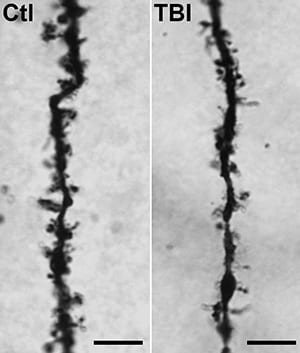

Atkins-Synaptic-Loss-after-TBI-300